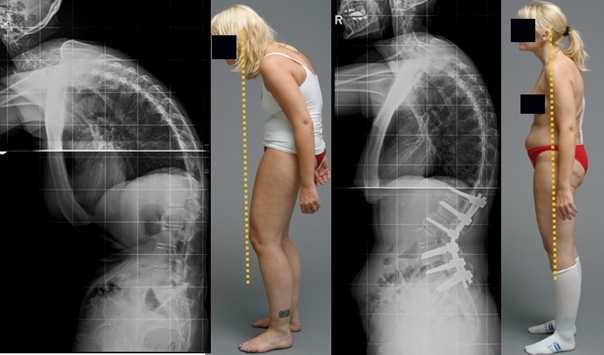

Guardate questa radiografia. È la colonna vertebrale di una persona di soli 44 anni, ma sembra quella di un vecchio. Una volta questi danni si riscontravano dopo i 60 anni, ma oggi è comune per chi ha appena più di 40 anni. Questi cambiamenti progrediscono con l’età, e ignorarli significa rischiare la perdita completa della mobilità!

Una delle poche soluzioni che la medicina può offrire è un’operazione complicata e rischiosa per rimuovere l'ernia e inserire perni metallici! Ma pensateci bene! Anche i migliori chirurghi ammettono che un intervento sulla colonna vertebrale è una misura estremamente sconsigliata e pericolosa, CHE PORTA SPESSO A PROBLEMI ANCORA PIÙ GRAVI, INFEZIONI, CONTAGI, COMPLICAZIONI E PERSINO ALLA MORTE!

Tutte le articolazioni richiedono attenzione, ma la colonna vertebrale è la priorità. Occupatevene prima che inizino i cambiamenti irreversibili. Ecco cosa attende chi non ha prestato attenzione ai segnali del proprio corpo: ERNIA, SPOSTAMENTO DELLE VERTEBRE, DEFORMAZIONE DELLA COLONNA VERTEBRALE, CURVATURA DELLA SCHIENA, COMPLETA PERDITA DI MOBILITÀ. Non aspettate il momento in cui anche il semplice movimento diventerà una tortura!

Guardate queste fotografie. Ecco cosa è successo a coloro che non hanno fatto attenzione ai sintomi. Oggi queste persone sono completamente senza speranza, e molti di loro non hanno nessuno su cui contare per le cure. Volete davvero un destino simile?